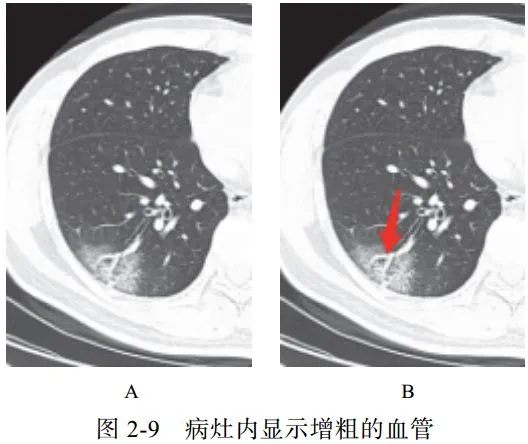

(九)血管增粗征

在亚实性病灶内部清晰显示血管走行,部分血管管径增粗,甚至比近端更粗

可能提示病理改变为血管周围间质水肿,并非血管内径增粗(图 2-9)